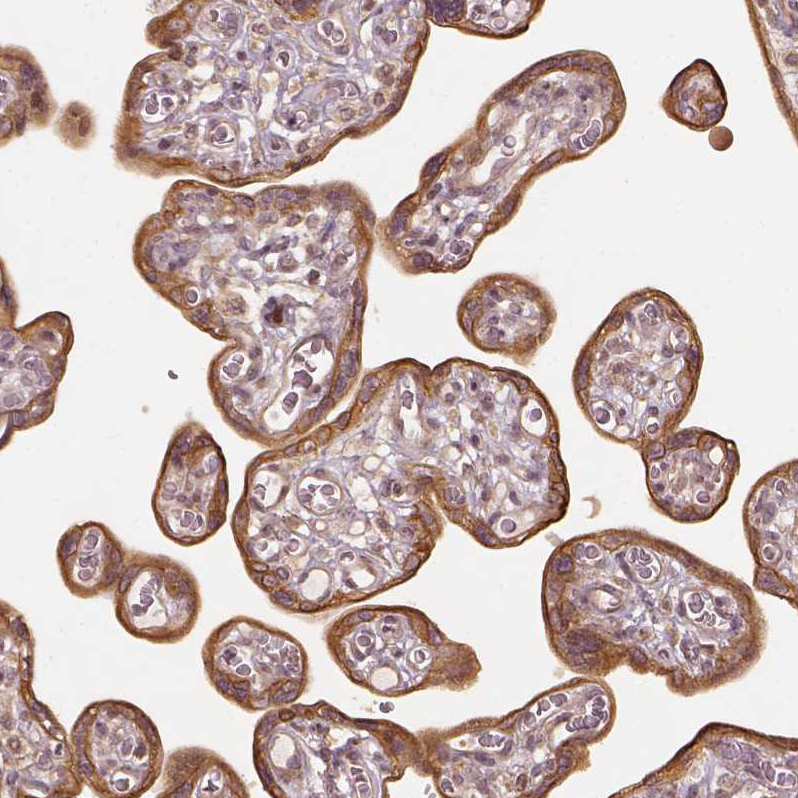

Immunohistochemical staining of human thyroid gland shows strong cytoplasmic positivity in glandular cells.